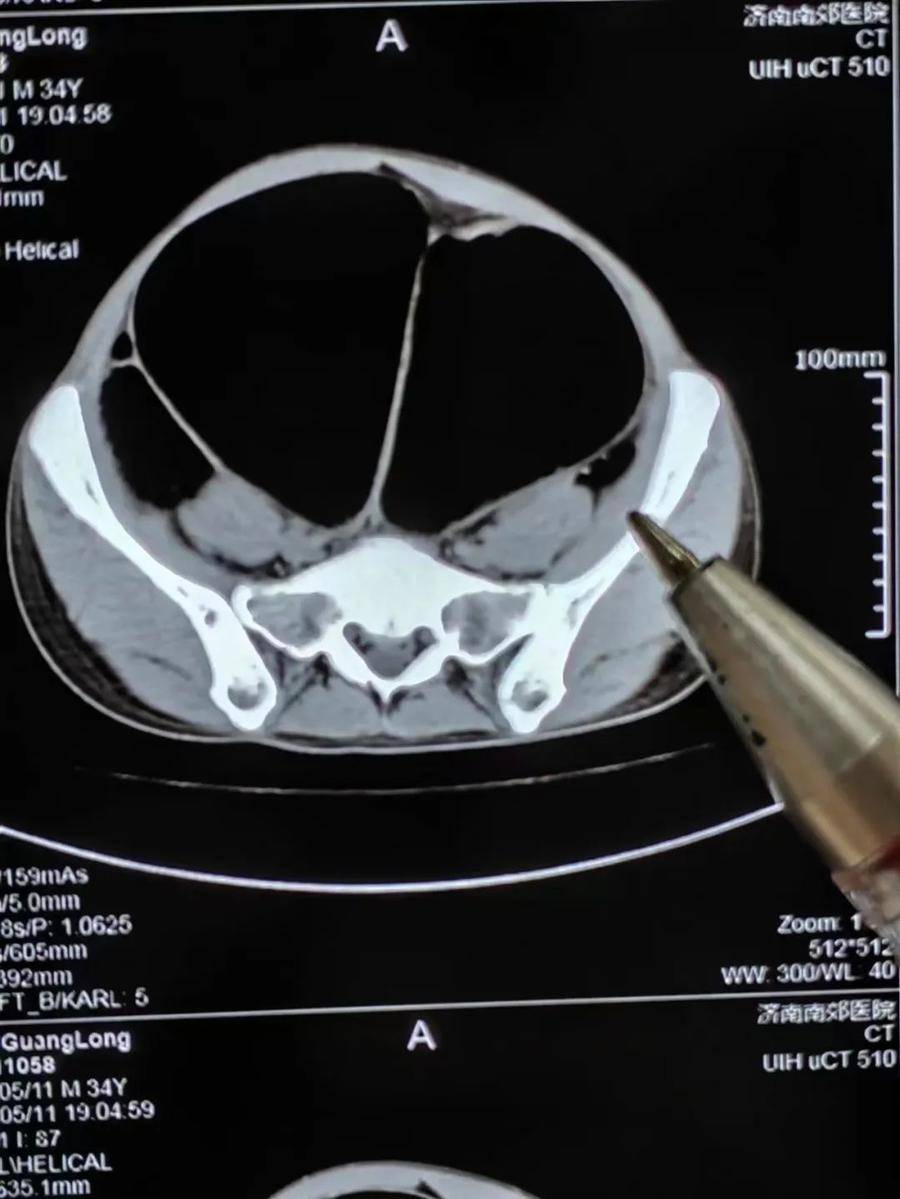

普外科王兆太主任团队接诊后,连夜为其制定治疗方案,完善相关检查。经过医学影像检查全腹CT显示:肠管明显扩张、积气,伴气液平面,降结肠远端管腔狭窄,局部显示不清,提示低位肠梗阻可能。